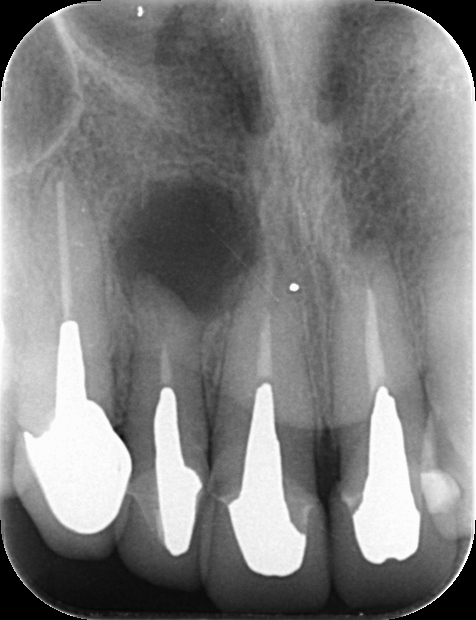

上顎側切歯再根管治療(抜歯回避症例)

性別:30代女性

部位:上顎側切歯

主訴:上顎側切歯の抜歯の可能性及び再根管治療の可否診断について他院よりご紹介.

3DCT及びデンタルX線撮影、及び歯周組織検査を行い保存可能と診断

90分のお時間を頂き、再根管治療を通法に従いラバーダム防湿下で施術終了